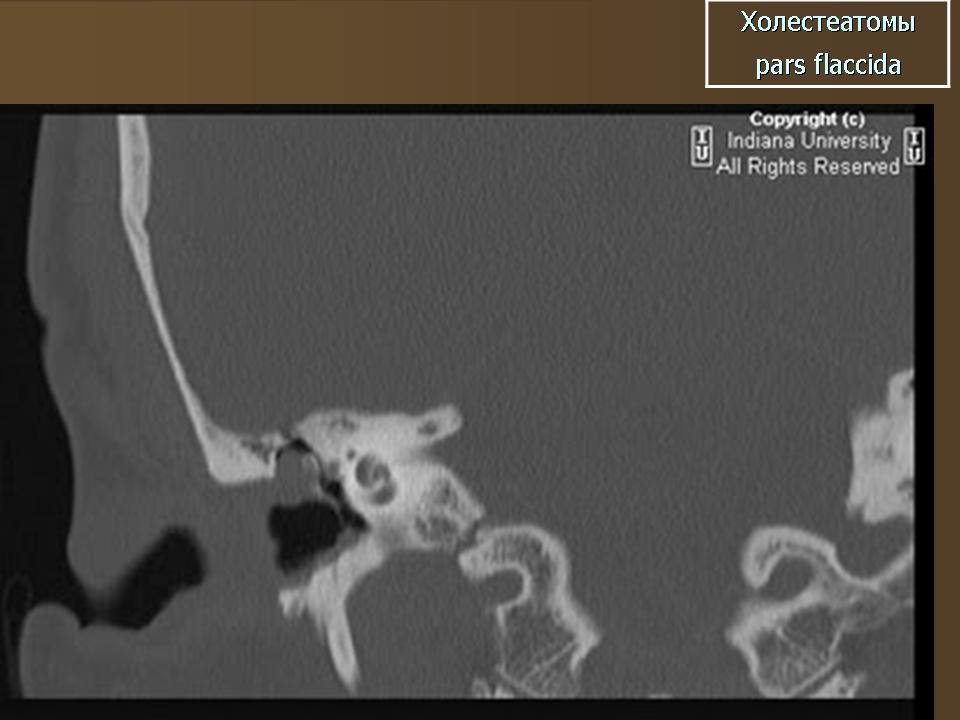

ID: 5467 Cholesteatoma - acquired Dr Frank Gaillard - 26 Jan 2009 CT through the temporal bone demonstrates a soft tissue mass in Prussak'...